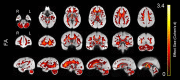

Aging is associated with widespread alterations in cerebral white matter (WM). Most prior studies of age differences in WM have used diffusion tensor imaging (DTI), but typical DTI metrics (e.g., fractional anisotropy; FA) can reflect multiple neurobiological features, making interpretation challenging. Here, we used fixel-based analysis (FBA) to investigate age-related WM differences observed using DTI in a sample of 45 older and 25 younger healthy adults. Age-related FA differences were widespread but were strongly associated with differences in multi-fiber complexity (CX), suggesting that they reflected differences in crossing fibers in addition to structural differences in individual fiber segments. FBA also revealed a frontolimbic locus of age-related effects and provided insights into distinct microstructural changes underlying them. Specifically, age differences in fiber density were prominent in fornix, bilateral anterior internal capsule, forceps minor, body of the corpus callosum, and corticospinal tract, while age differences in fiber cross section were largest in cingulum bundle and forceps minor. These results provide novel insights into specific structural differences underlying major WM differences associated with aging.